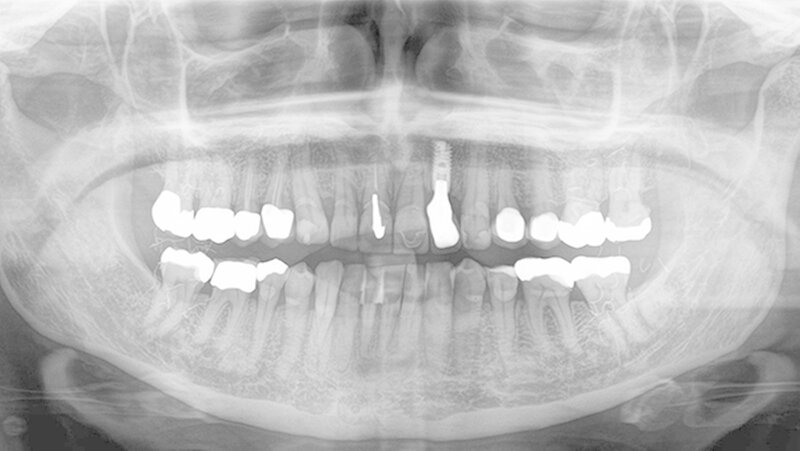

Schon wenige Wochen nach dem Eingriff habe man den erfreulichen Effekt des Liftings erkennen können, berichtet die Patientin: „Die hängenden Lippen wurden gestrafft und der positive Effekt war sichtbar“. Die Goldfäden verblieben für immer im Gewebe. Der Patientin zufolge haben sich in den letzten Jahren durch Muskelbewegungen einige Goldfäden verschoben und wurden extradermal sichtbar: „Diese Fäden ziehe ich mir dann aus der Haut heraus. Sie sind hauchdünn und kaum zu erkennen, aber mir als Kosmetikerin fällt dies natürlich sofort auf.“

Durch die Altersveränderungen der Haut, dem Absinken der Weichteilstrukturen und dem Verlust an Fettgewebe, haben sich in den vergangenen Jahren vermutlich die Goldfäden aus der Wangenhaut nach kaudal verlagert und sind im OPG jetzt sichtbar geworden. Von zahnärztlicher Seite wurde nichts weiter unternommen.